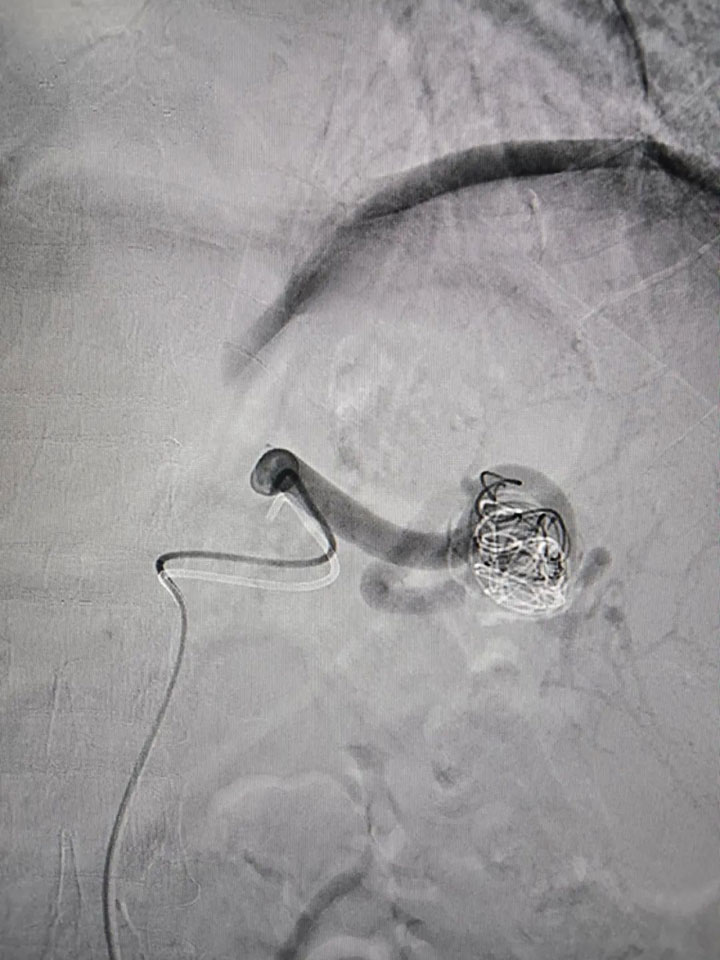

经过完善的术前评估,普外科邀请集团普外医疗中心血管外科桂锐主任、胡玉东主任,仅在股动脉做一2cm小切口,通过一根导丝,精准定位瘤体位置,将弹簧圈置入瘤腔,顺利完成手术。

“患者的脾动脉瘤直径较大,属于囊状动脉瘤,瘤体向动脉一侧偏心性扩张,这类口袋状的动脉瘤,破裂的风险更高,占总数的75%。患者发现及时,手术顺利,很幸运。”胡玉东主任说。

经过严格的术后管理,患者第二天已经可以下床活动。导丝代替手术刀,无孔不入的介入手术,对比开放手术,不仅定位准确、创伤小、见效快、而且痛苦少、恢复快、并发症少、疗效好,以及简便安全等诸多优点。目前,脾动脉瘤介入治疗(包含脾动脉瘤腔内隔绝术、弹簧栓塞术伴/不伴裸支架辅助等)成为动脉瘤疾病的首选治疗方法。依托集团普外科医疗中心技术优势,广济医院普外科让患者在家门口享受到三级甲等综合性医院的医疗服务,常规开展动脉瘤支架植入,脾动脉栓塞,肝恶性肿瘤化疗栓塞,PTCD,ERCP等肿瘤血管介入手术治疗。